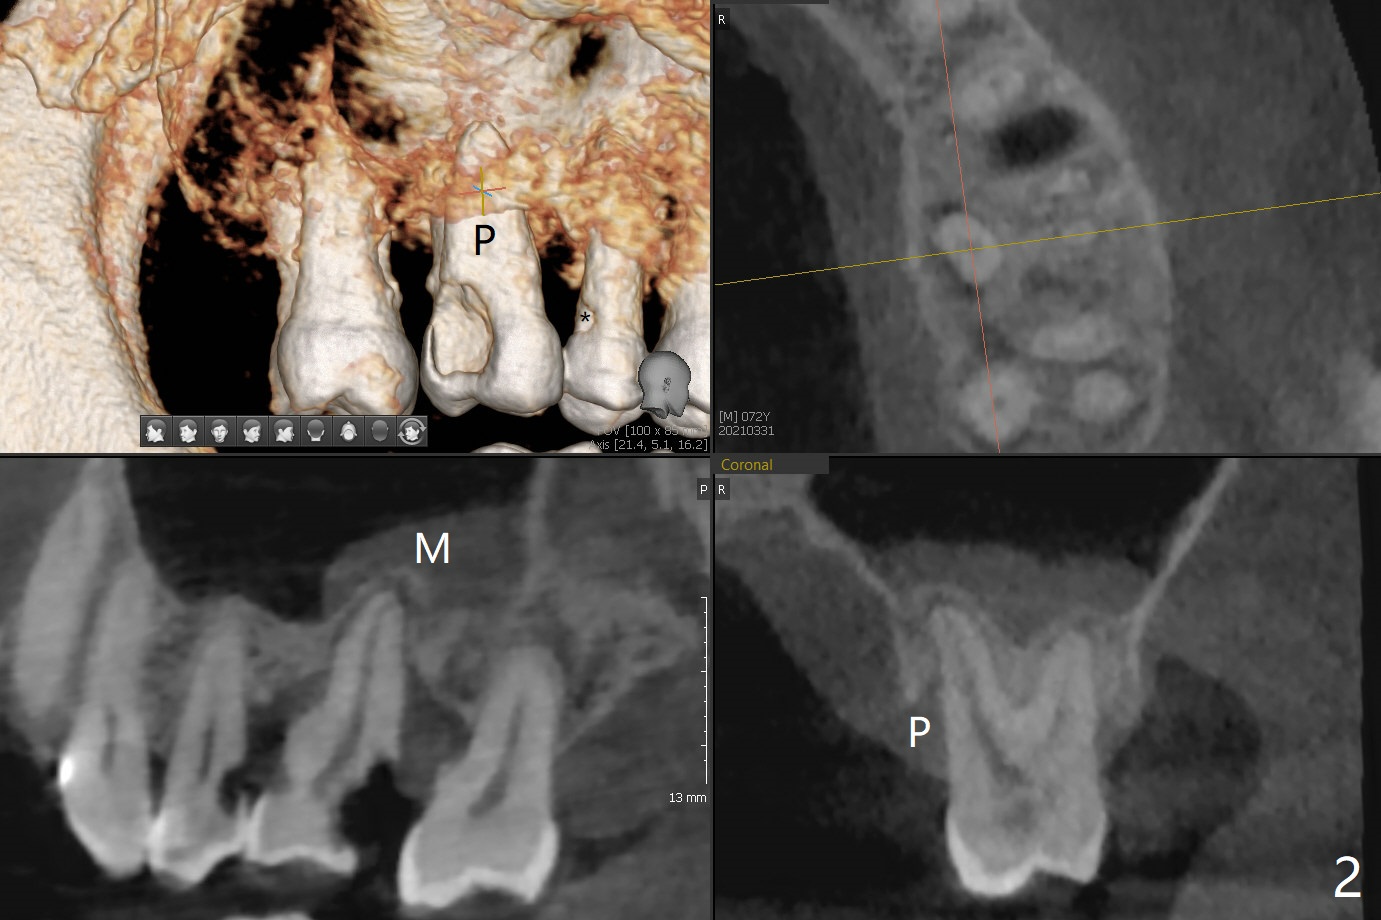

72岁男14号牙腭侧根尖接近上颌窦(图一,二:P),牙齿拔除后,根尖对刮治敏感,冲洗后,开始导板钻洞,圆钻穿透窦底,放置粘性骨粉和报废植体提升(图三:箭头)。放置小张PRF和骨粉(图四:箭头),植入正式植体,基台和骨粉(图五:*),最后覆盖PRF(图六),为了防止骨粉从邻牙牙龈沟(>)丢失,覆盖树脂敷料。基台和前后邻牙使树脂敷料术后一周巍然不动(图七:A)。术后一个月撤除树脂敷料,牙槽窝已经愈合(图八)。再过两周牙槽窝上皮好像进一步成熟(图九),然后塞入一个龈线,制备临时牙冠。